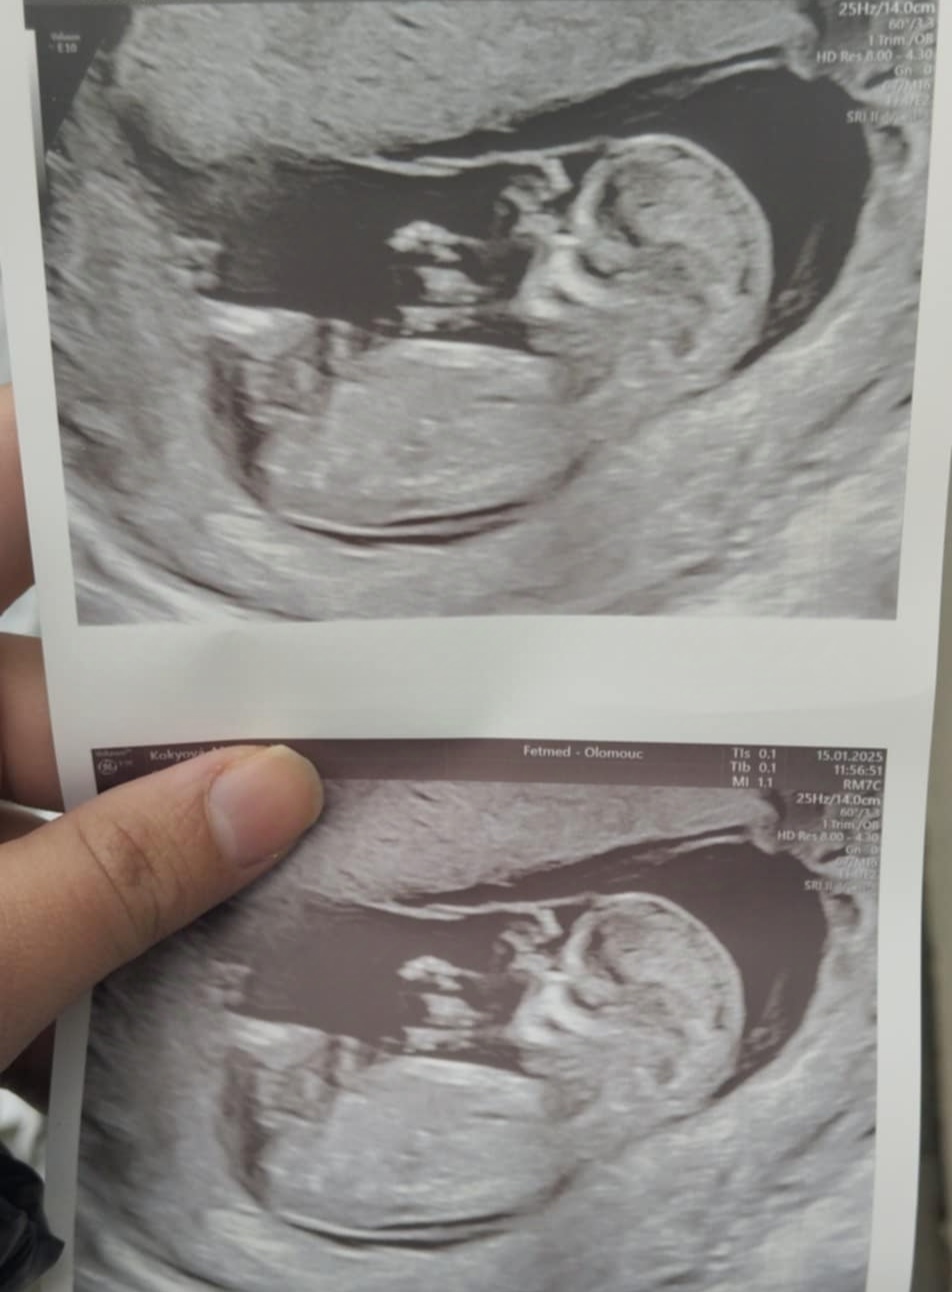

Určitě tě nemine 3D ultrazvuk.

Nebo také screening v 1. trimestru.